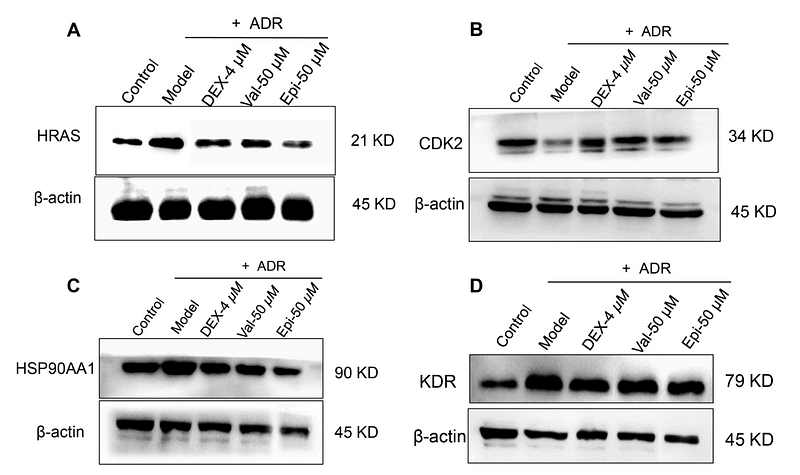

4-hydroxysesamin protects rat with right ventricular failure due to pulmonary hypertension by inhibiting JNK/p38 MAPK signaling

Author: Lingnan Zhang, Xinshun Gu

PMID: 38728253

期刊: Aging-Us

应用: WB

反应种属: Rat

发表时间: 2024 May